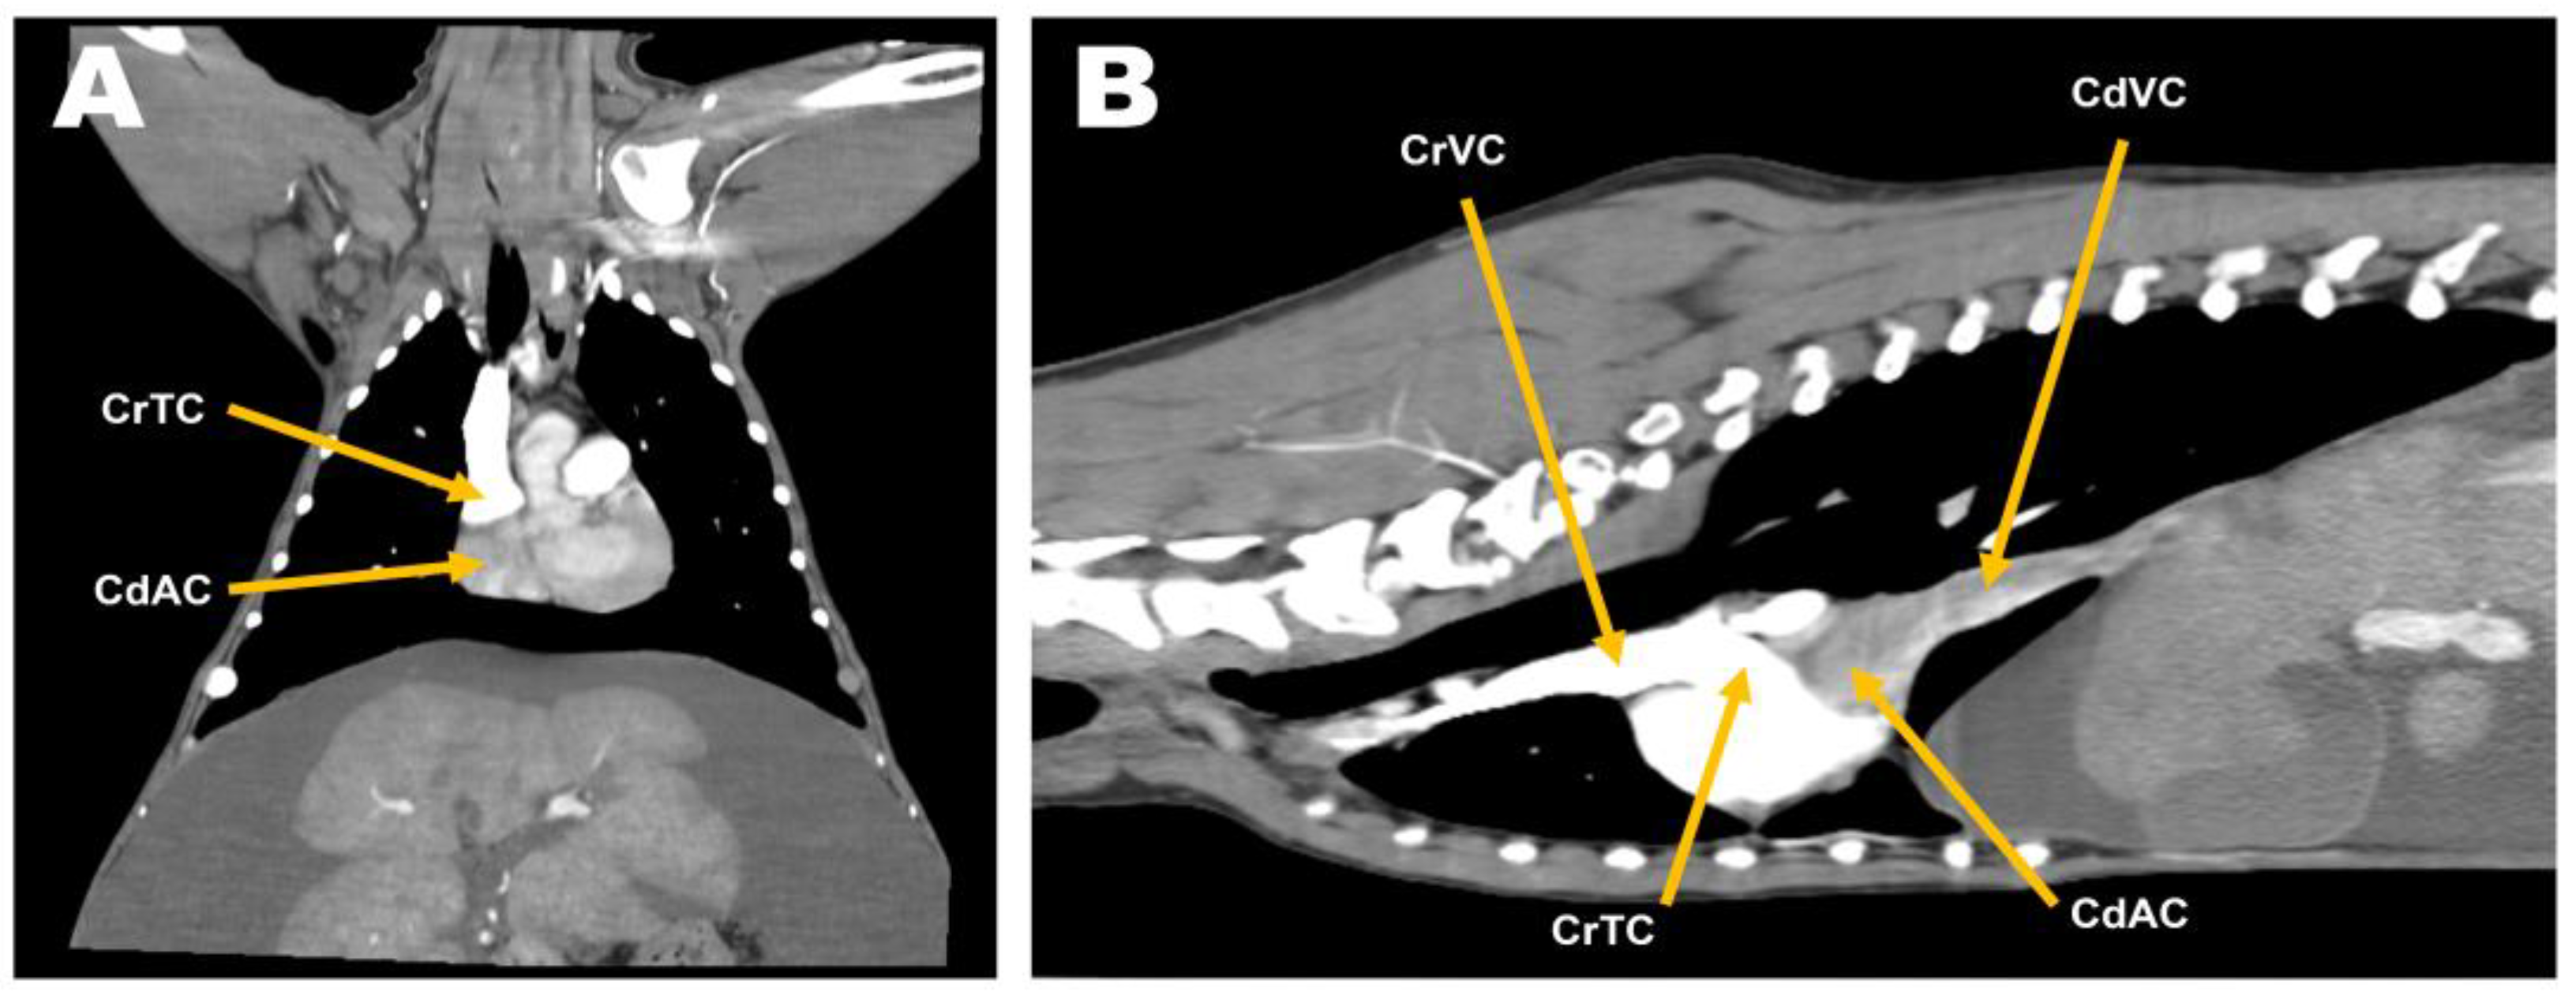

The patient underwent preoxygenation with 100% oxygen via the flow-by technique. Preanesthetic medication consisted of diphenhydramine (2 mg/kg, SC; Diphenhydramine HCl Inj., Mylan Ireland), dexamethasone (0.2 mg/kg, IV; Dexamethasone Inj., Jeil ROK), maropitant (1 mg/kg, SC; Cerenia, Zoetis Spain), and cefazolin sodium (22 mg/kg, IV; Cefazolin, Jonggeundang ROK). Propofol (1 mg/kg, IV; Anepol, Hana ROK) and midazolam (0.2 mg/kg, IV; Midazolam Inj., Bukwang ROK) were administered slowly, followed by propofol (4 mg/kg, IV; Anepol, Hana ROK). Anesthesia was maintained using isoflurane (Ifran, Hana ROK). For analgesia, a mixture of lidocaine and bupivacaine (0.2 mg/kg, each; Lidocaine Inj., Jeil ROK; Bupivacaine HCl Inj., Myungmoon ROK) was injected into the intercostal space for intercostal block, and a constant-rate infusion of fentanyl (5 mcg/kg/min; Fentanyl Citrate Inj., Myungmoon ROK) was subsequently administered. When an adequate depth of anesthesia was achieved, the patient was positioned in left lateral recumbency, with the right hind limb reflected for cannulation of the arterial line. The forelimbs were secured in an extended position to prevent limb movements associated with spasms of the extrinsic musculature during thoracotomy. First, the femoral triangle was accessed, and a 5-fr cannula was inserted into the femoral artery using the modified Seldinger technique to measure invasive blood pressure (IBP) in real-time. Subsequently, a right-fifth intercostal thoracotomy was performed using a cardiac approach. For VIO, Rommel tourniquets were placed around the CrVC and CdVC (Figure 4A). In order to facilitate the right atriotomy, a ventral incision of the fibrous pericardium below the phrenic nerve followed by pericardial tenting was performed using 2-0 silk sutures.

Heparin (100 IU/kg) was administered intravenously, and to induce mild hypothermia with a target body temperature of approximately 34.5 °C in the patients, the thermally controlled pad and fluid warmer, which had been used to prevent unintended hypothermia, were discontinued. It took approximately 10 min for the body temperature to decrease to 34.5 °C. Subsequently, a partial VIO was initiated by tightening the tourniquets placed on the CrVC and CdVC. After atriotomy, the cardiac interior was carefully inspected, and the remnant membrane was excised using Metzenbaum scissors (Figure 4B). A vascular clamp was applied to the atriotomy site, and the partial VIO was discontinued. The vascular clamp was then slightly released to allow for de-airing of the atrium, confirming the spillage of a small amount of venous flow and subsequent re-clamping (Figure 4C). The atriotomy site was closed using a two-layer simple continuous pattern with a 6–0 polypropylene suture (Figure 4D). The total duration of partial VIO was 3 min and 30 s, and vital signs returned to normal shortly after the cessation of VIO. No specific abnormalities were observed on arterial blood gas analysis. After completing the intrathoracic procedure, the thoracic cavity was lavaged with warm saline and inspected for air leakage or hemorrhage. To increase the patient’s body temperature, the thermally controlled pad and the fluid warmer were reapplied. A thoracostomy tube was placed intercostally and the surgical site was closed routinely. The arterial line was removed and the femoral artery closed using a simple interrupted pattern with a 6–0 polypropylene suture.

Four days after the procedure, the patient showed normal demeanor and appetite, with no residual ascites (Figure 5A,B). On echocardiography, on day 6 after surgery, normal right atrial flow was detected with no residual obstruction between the cranial and caudal right atrial chambers (Figure 5C,D). There were no specific complications, such as re-stenosis or recurrence of clinical signs related to CTD at the 1-year postoperative follow-up.

Figure 4. Surgical procedure of partial venous inflow occlusion for membranectomy. (A) Preplacement of the Rommel tourniquets (black line) around the cranial and caudal vena cava (blue line). (B) Excision of the remnant membrane after right atriotomy. (C) Re-clamping of the vascular clamp after de-airing of the right atrium. (D) Closure of atriotomy site using two-layer simple continuous pattern. Cr, cranial; Cd, caudal; D, dorsal; V, ventral.